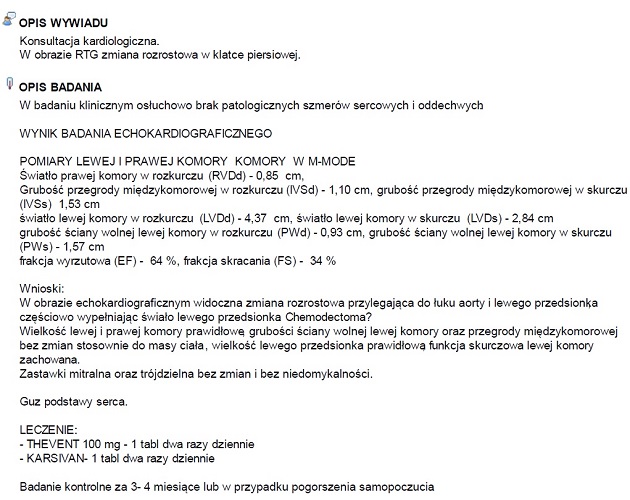

Goldi był dzisiaj na wizycie u kardiologa. Wykonano mu badanie echokardiograficzne serca, które wykazało widoczną zmianę rozrostową przylegającą do łuku aorty i lewego przedsionka.

Staruszek ma zalecone leki oraz badanie kontrolne za 3-4 miesiąca lub w przypadku pogorszenia samopoczucia.

Goldi był dzisiaj na wizycie u kardiologa. Wykonano mu badanie echokardiograficzne serca, które wykazało widoczną zmianę rozrostową przylegającą do łuku aorty i lewego przedsionka.

Staruszek ma zalecone leki oraz badanie kontrolne za 3-4 miesiąca lub w przypadku pogorszenia samopoczucia.

14-letni Goldi czuje się dobrze, dostaje regularnie Karsivan, Theovent i suplementy na stawy. Niedługo czeka go wizyta kontrolna u kardiologa. W listopadzie 2018 po wizycie u kardiologa stwierdzono: Wykonano mu badanie echokardiograficzne serca, które wykazało widoczną zmianę rozrostową przylegającą do łuku aorty i lewego przedsionka.